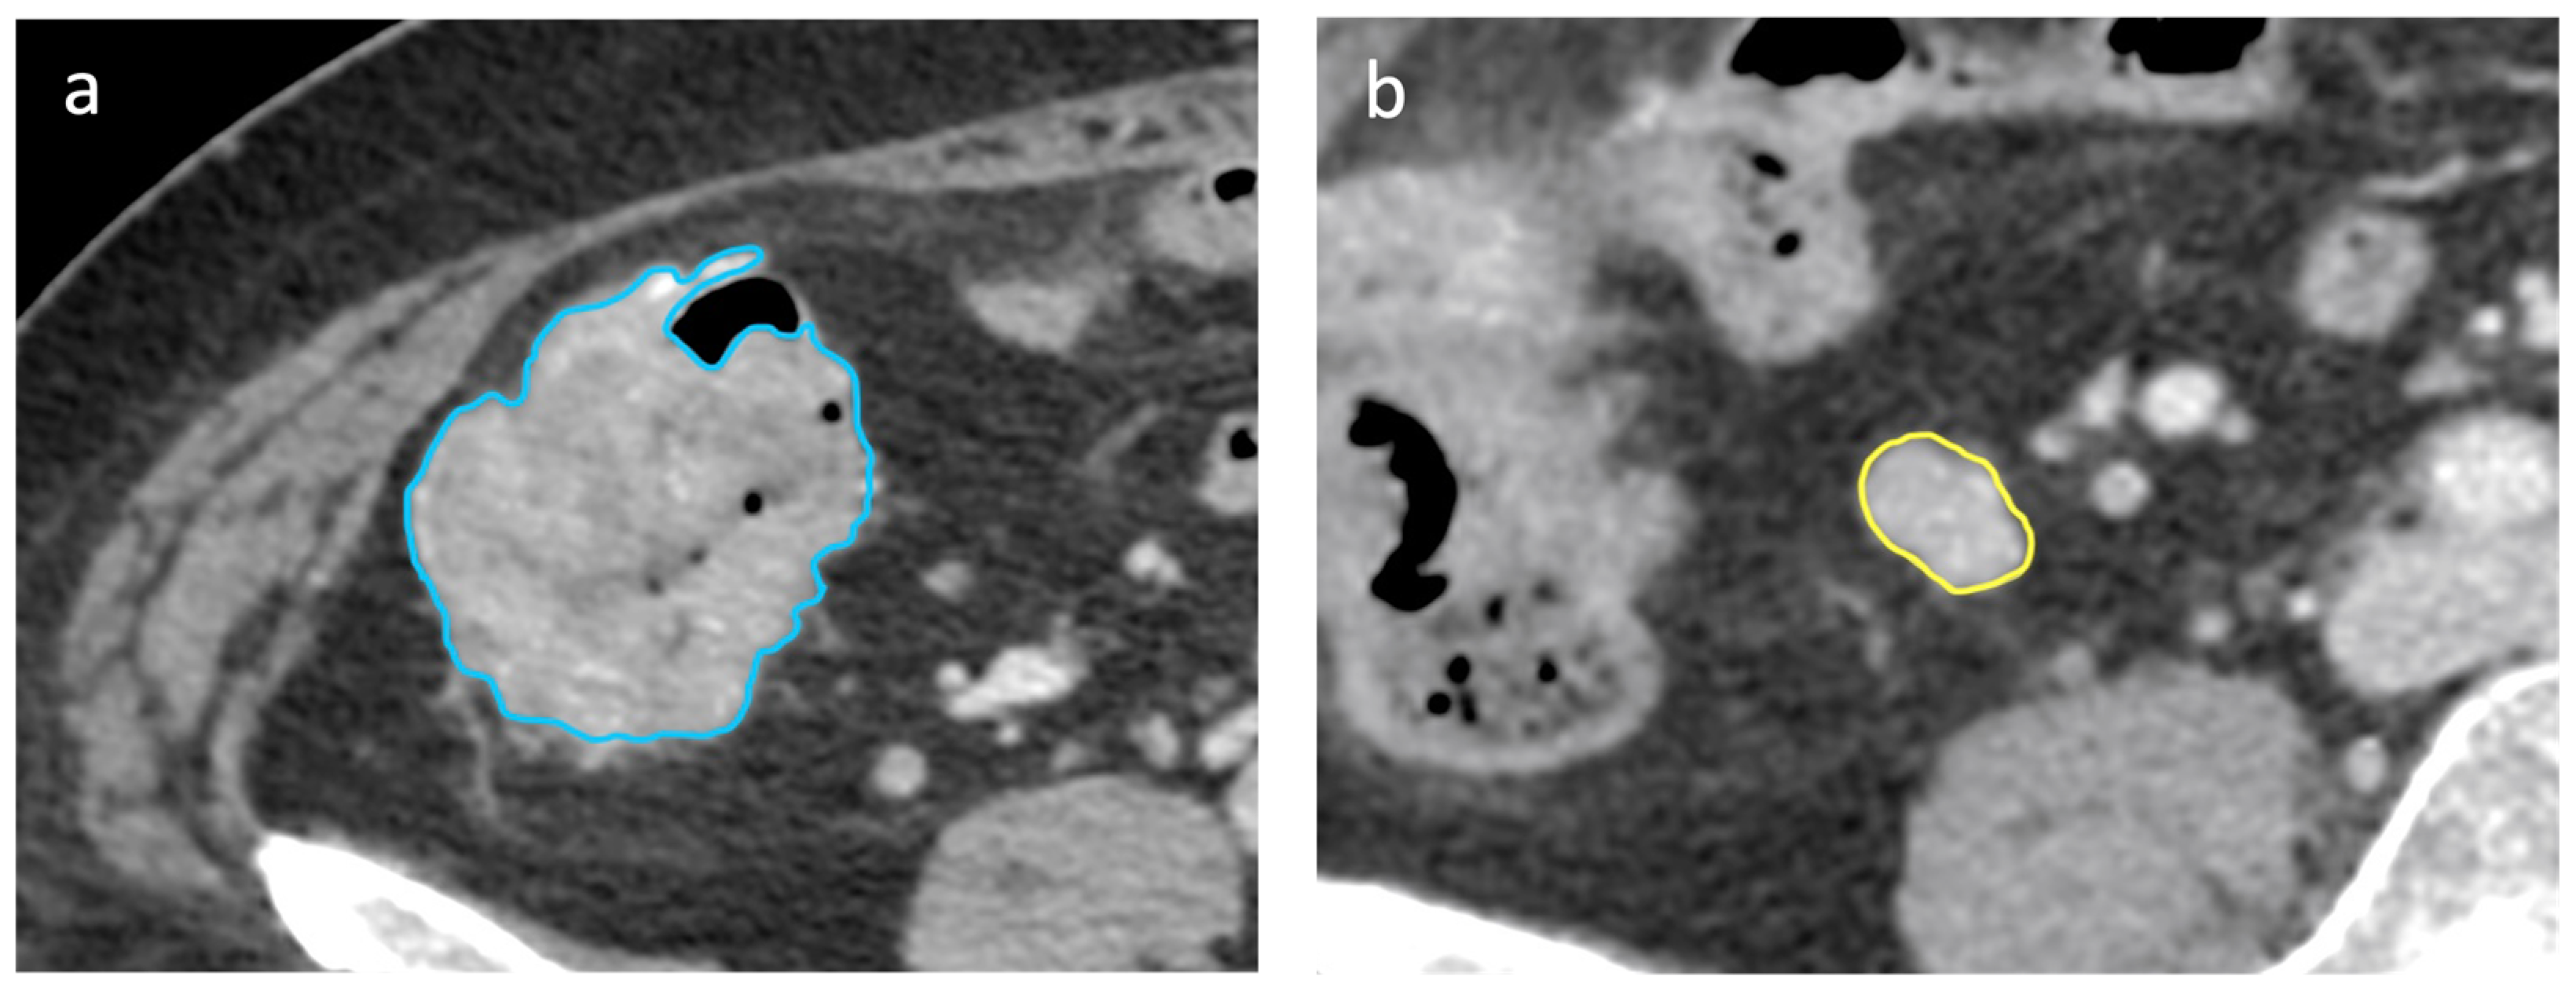

2.4. CT Scan Segmentation Analysis

2.5. Radiomic Features Extraction

3.3. D Segmentation and LN’s Radiomic Features